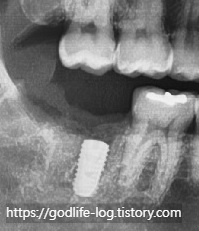

위 사진의 경우 사랑니 때문에 충치가 너무 심해져서 치아를 더 이상 살릴 수 없는 경우이고 발치가 필요한 상황입니다.

하지만 잇몸 뼈 자체는 다른 부분이랑 비슷하게 잘 유지되고 있기 때문에 사랑니와 충치가 심한 치아 함께 발치 후 바로 임플란트를 식립 할 수 있습니다.